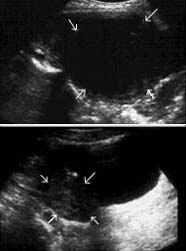

I was browsing to found out how big it is inside just to show you, since I haven’t received my sonogram test from the hospital as of yet. I found a sonogram pic from http://www.mirs.org/fibroids.htm

grapefruit size (10 cm) fibroid